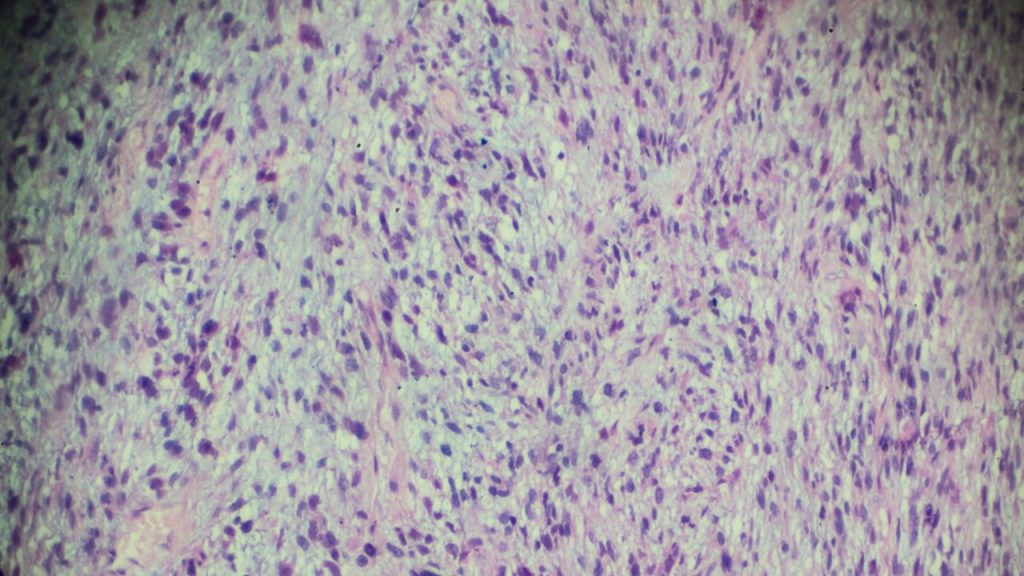

پزشک متخصص در ابتدا برای تشخیص توده سرطانی با انجام آزمایش بیوپسی، نمونهای از بافت تومور شما را مورد بررسی قرار میدهد. بعد از بیوپسی، آسیبشناس به بافت سرطانی زیر میکروسکوپ نگاه میکند و یک گزارش پاتولوژی را به انکولوژیست جراحی ارائه میدهد.